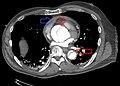

Computed tomography

Computed tomography angiography is a fast, noninvasive test that gives an accurate three-dimensional view of the aorta. These images are produced by taking rapid, thin-cut slices of the chest and abdomen, and combining them in the computer to create cross-sectional slices. To delineate the aorta to the accuracy necessary to make the proper diagnosis, an iodinated contrast material is injected into a peripheral vein. Contrast is injected and the scan performed using a bolus tracking method. This type of scan is timed to an injection to capture the contrast as it enters the aorta. The scan then follows the contrast as it flows through the vessel. It has a sensitivity of 96 to 100% and a specificity of 96 to 100%. Disadvantages include the need for iodinated contrast material and the inability to diagnose the site of the intimal tear.